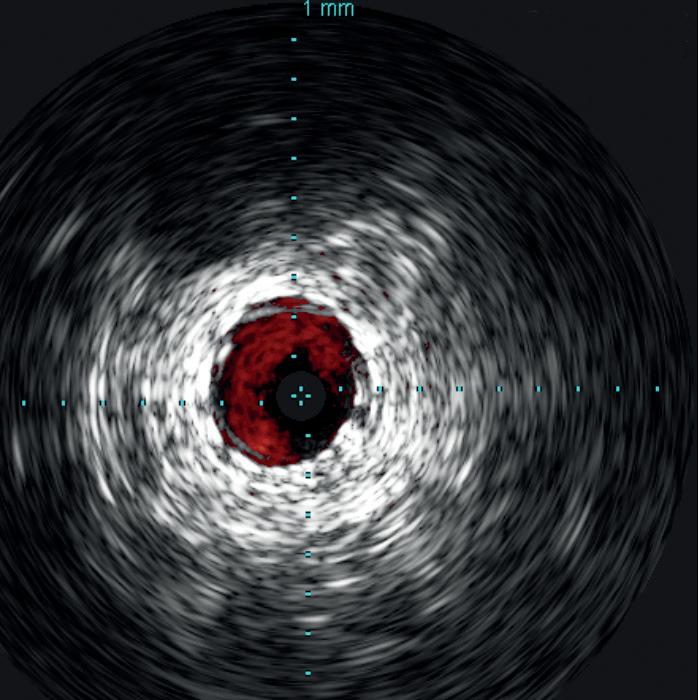

the Stellarex drug-coated balloon (DCB). Completion arteriogram showed marked improvement in flow but a possible dissection in the mid-segment of the SFA. IVUS’ unique ChromaFlo feature was then used to identify and confirm the areas of dissection (see figure 2) Most of the vessel had significant luminal gain but there were multiple areas of short-segment dissection. These were then treated with placement of a total of six Tack Endovascular System implants. The Tack implants were then post-dilated using plain old balloon angioplasty (POBA). Completion angiogram and IVUS (see figure 3) demonstrated resolution of the dissections. Follow-up ABI was 0.95 at rest.

The benefits of utilizing IVUS have been shown in the literature. In nearly every vascular bed studied, we have seen an improvement in overall outcomes. Over the last several years, especially with the introduction of DCBs, as well as atherectomy, there has been a move away from utilizing the use of stents to minimize in-stent restonosis, stent fractures and stent thrombosis. The Tack system optimizes percutaneous transluminal angioplasty (PTA), especially with DCB therapy, to individually treat dissections and to avoid the need to place long segments of stents. In reviewing data on PTA with Tack and PTA alone, there was a marked improvement in the primary patency of 67–87% in patients treated with a DCB compared to 95% 12-month patency in patients treated with DCB and Tack.4 This case shows the